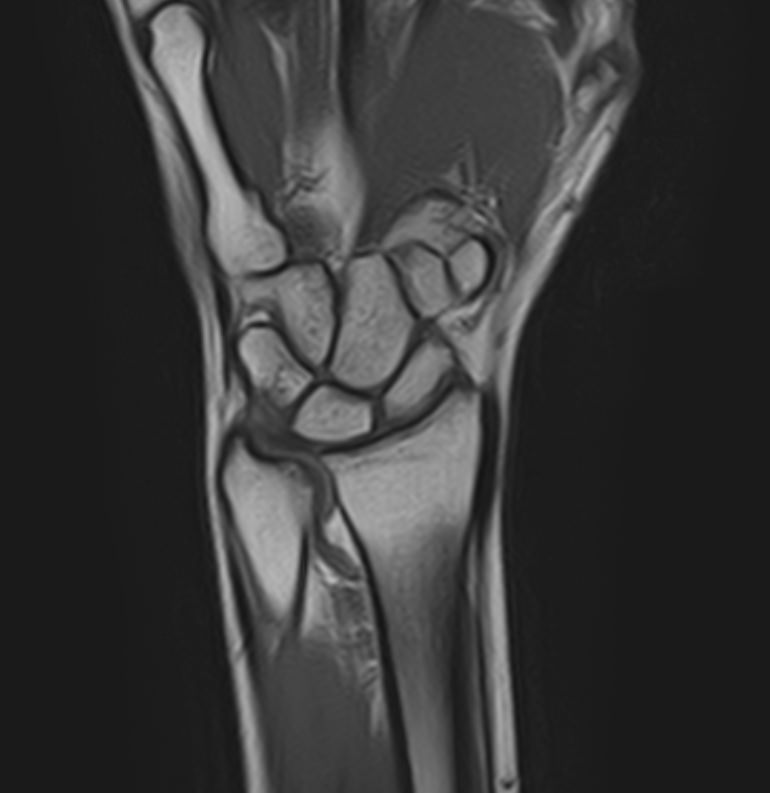

МРТ является современным высокоинформативным неинвазивным и при этом безопасным методом исследования, который позволяет детально визуализировать состояние всех структур лучезапястного сустава, включая дистальные отделы лучевой и локтевой костей, хрящей, сухожилий, нервов и окружающих мягких тканей.

В клинике «Доступная медицина» исследование проводится на новейшем высокопольном томографе экспертного класса TOSHIBA VANTAGE TITAN 1,5 Тесла, который делает послойное сканирование исследуемой области в различных плоскостях с шагом от 1 мм и в дальнейшем преобразует полученные данные в трехмерные изображения. Результаты МРТ позволяют выявлять заболевания лучезапястного сустава на начальных стадиях и назначать своевременное лечение.